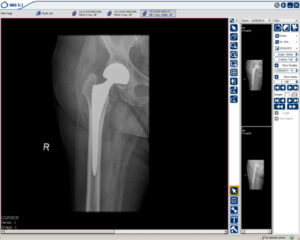

Mobilitas Cepat: Penggantian Pinggul Memungkinkan Penyanggaan Beban Segera untuk Wanita Berusia 70 Tahun

Contoh dari seorang wanita berusia 70 tahun yang patah tulang pinggul dan menjalani penggantian pinggul sehingga segera mampu berdiri lagi.